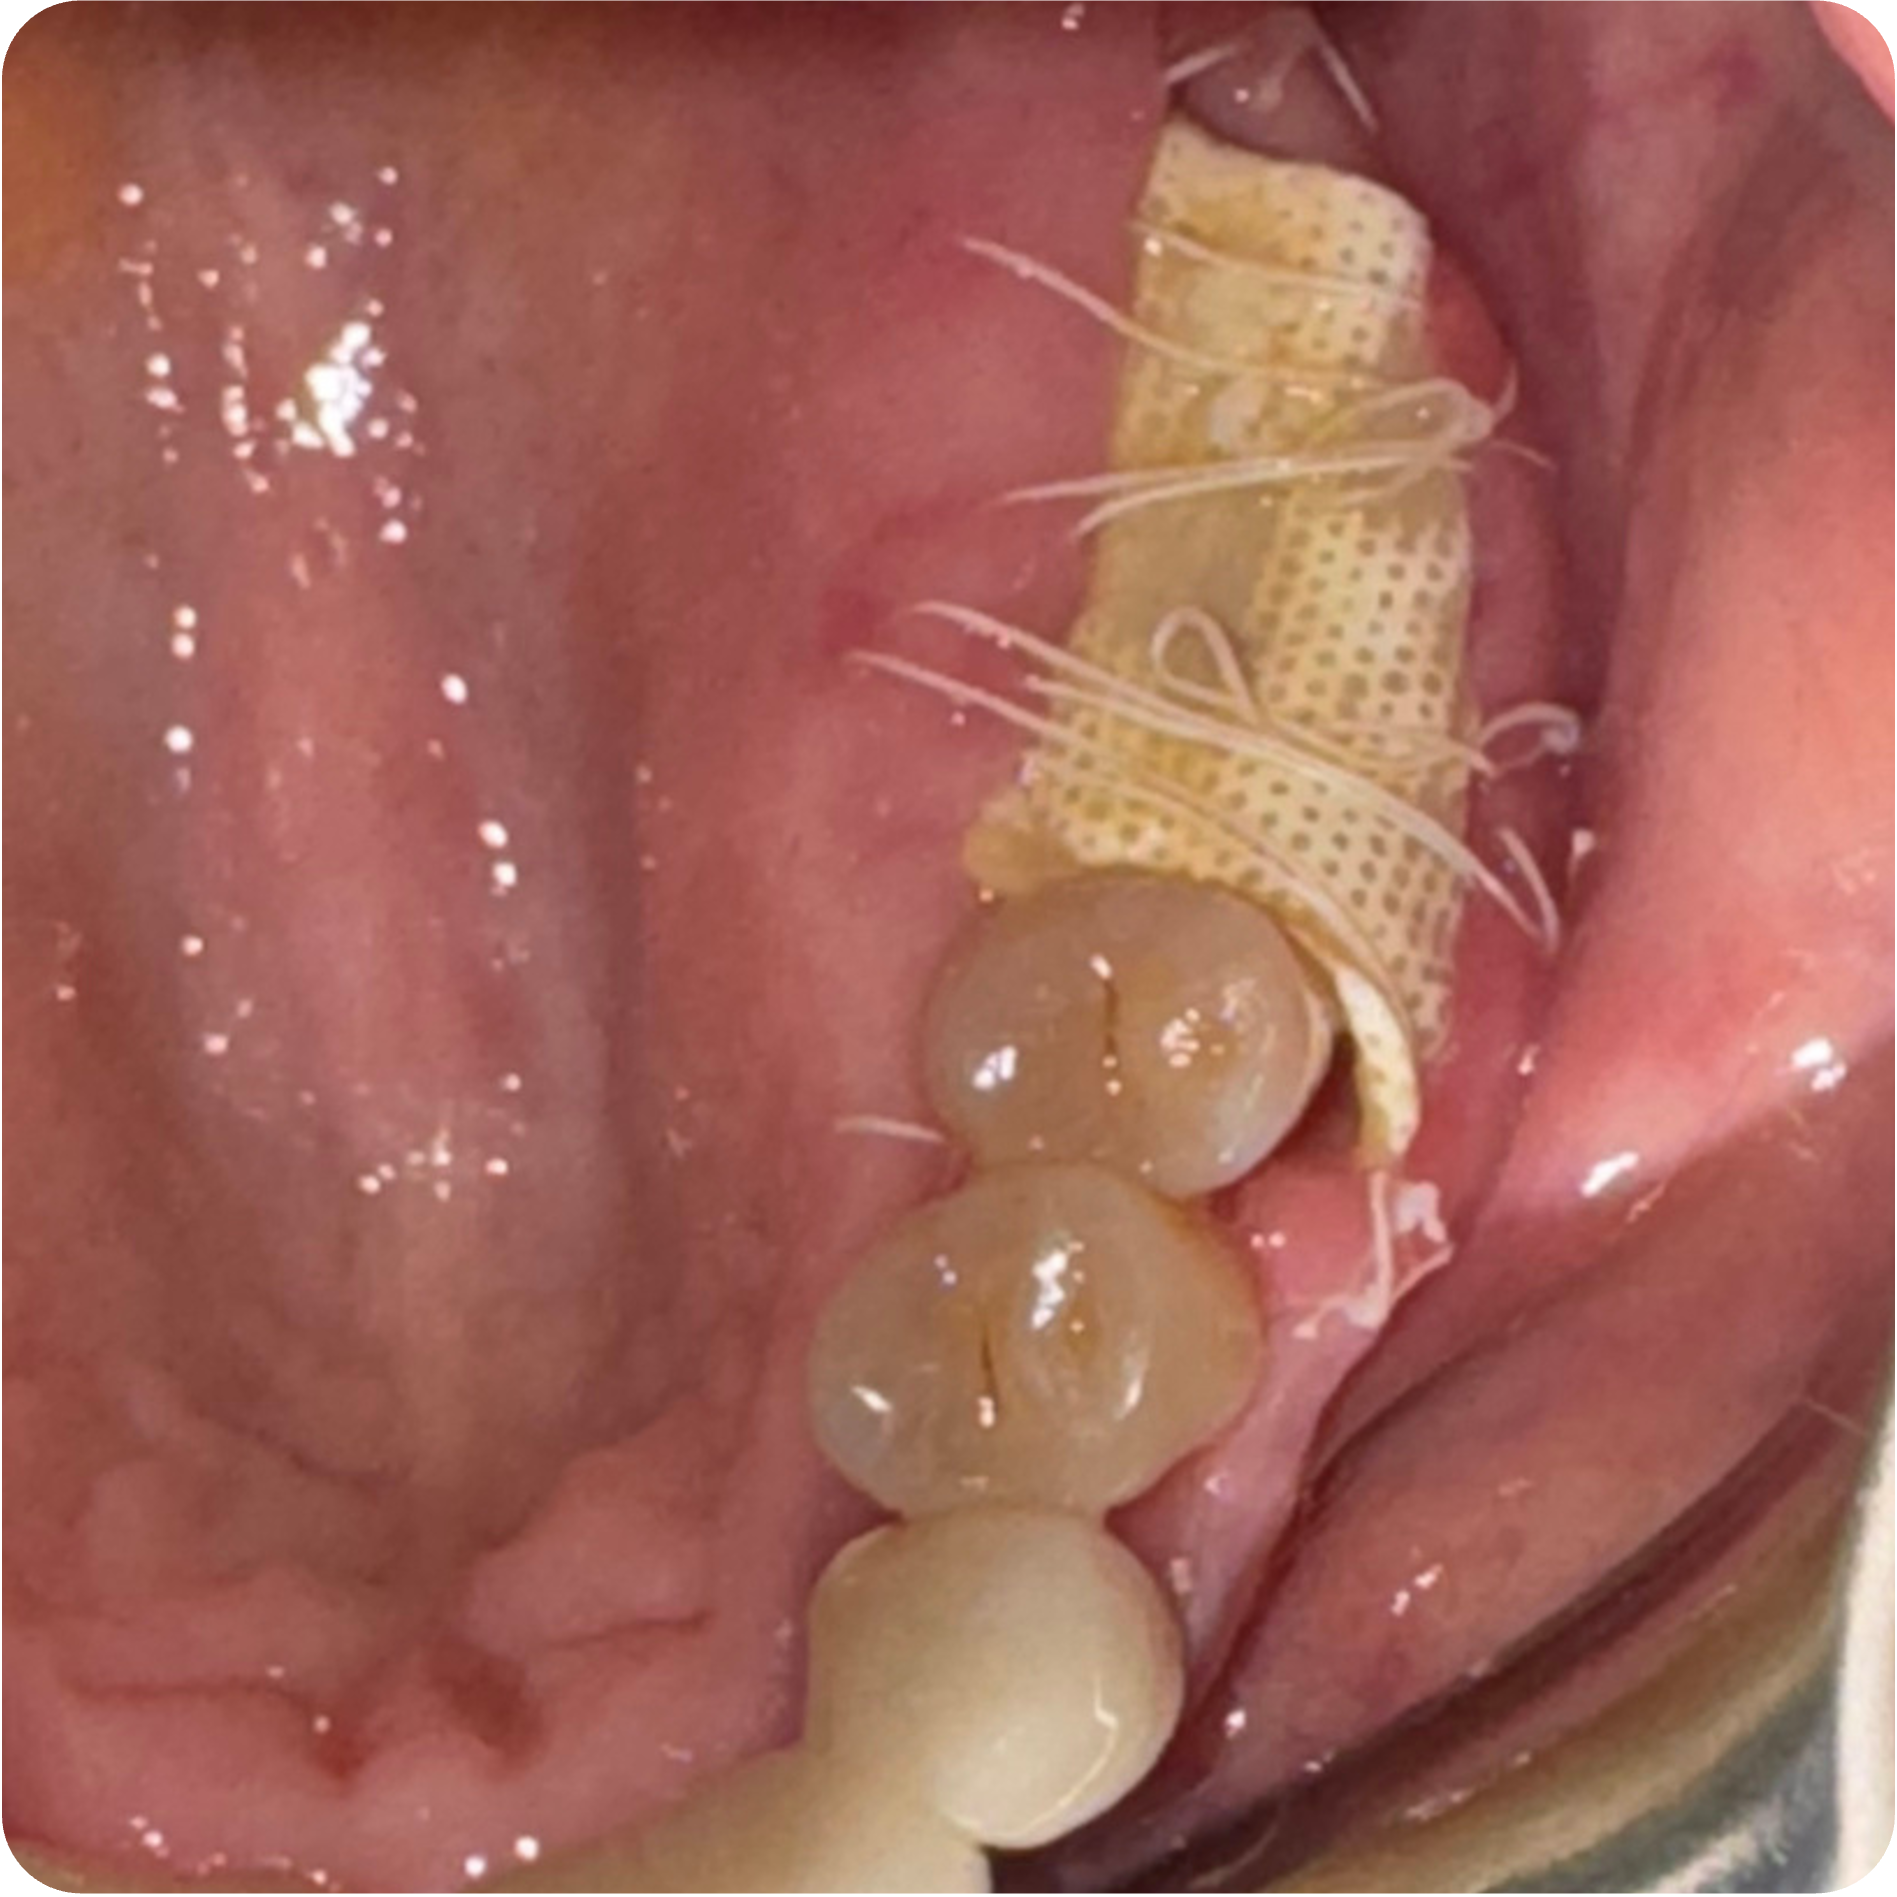

May 22, 2025Extractions with bone grafting (#2, #3, #30, #31) + Covered Socket Residuum (CSR) ~ Previously known as cavitation ~ protocols (#1 and #32) with protection protocol (lower right & upper right).

June 06, 2025Suture removal for the May 22 surgical sites.

June 12, 2025Membrane removal for #2, #3, #30, and #31 surgical sites.

Visual Case Progression

All clinical images are shown at a consistent size for easy comparison.

- Guided Open Wound Healing Protocol (GOWH): Extractions and Covered Socket Residuum (CSR) ~ Previously known as cavitation ~ sites were treated following the Guided Open Wound Healing Protocol developed by Professor Shahram Ghanaati, MD, DDS, PhD. This protocol focuses on thorough debridement, biological tissue management, and optimized healing conditions to support predictable bone regeneration and reduce inflammatory burden.

- Staged Extractions with Guided Bone Regeneration: Compromised teeth were removed atraumatically and grafted to preserve bone volume and create stable foundations for future implants.